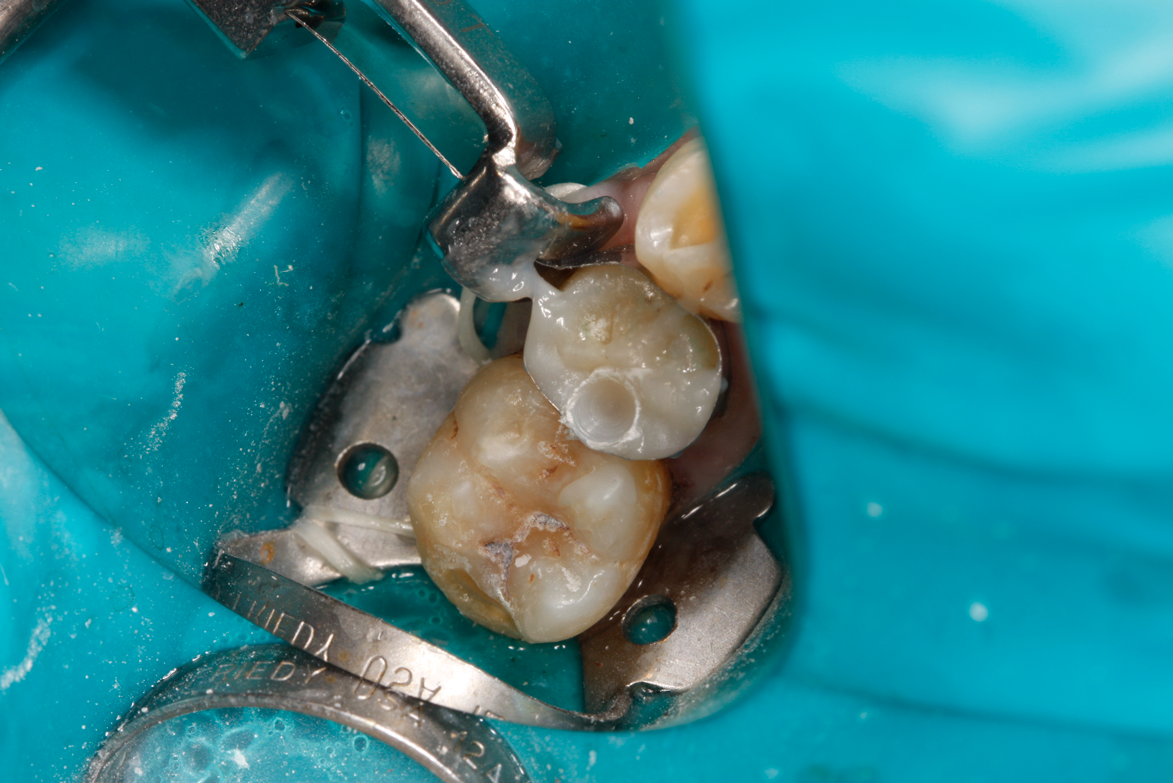

Fig 10. Occlusal approach was successful in the placement of a dual-cured bulk-fill flowable. Note the depth of box form.

Figure 10

Fig 11. Final preparation after gingitage with coarse diamond bur to remove soft tissue from the cavity in tooth No. 2.

Figure 8A is a radiograph revealing deep root caries previously restored temporarily by a resident at the AEGD Residency Program clinic with glass ionomer utilizing a lateral rather than occlusal approach. After the glass ionomer failed to adhere, another resident again attempted a lateral approach that resulted in the restoration shown in Figure 8B. A third resident had success with an occlusal approach, removing a failed occlusal composite to access the distal  (Figure 9). This attempt was successful both in the preparation of the lesion and in the placement of a dual- cure bulk-fill flowable (Bulk EZ Plus, Zest Dental Solutions; alternatively: HyperFIL®, Parkell; Fill-Up!, Coltene) extruded through a bendable needle (Figure 10). Figure 11 shows the final preparation after tissue removal was accomplished with rotary gingitage; note that this was performed with the rubber dam in place. An air abrasion device (Groman Etchmaster, Groman Dental; alternatively: PrepStart H2O, Zest Dental Solutions; Bioclear Blaster, Bioclear) was used with potassium bicarbonate to remove biofilm prior to acid etching (Figure 12). Phosphoric acid 37% was utilized in a total etch fashion (Fig- ure 13 and Figure 14) for 20 seconds. Figure 15 shows the universal bond (Scotchbond Universal, 3M; alternatively: All-Bond Universal®, BISCO; Prelude One, Danville Materials) with metha- cryloyloxydecyl dihydrogen phosphate (MDP) being scrubbed into the cavity for 20 seconds. After air thinning for 20 seconds, the adhesive was light cured for 40 seconds at 1,200 mw/cm2power density (Figure 16).